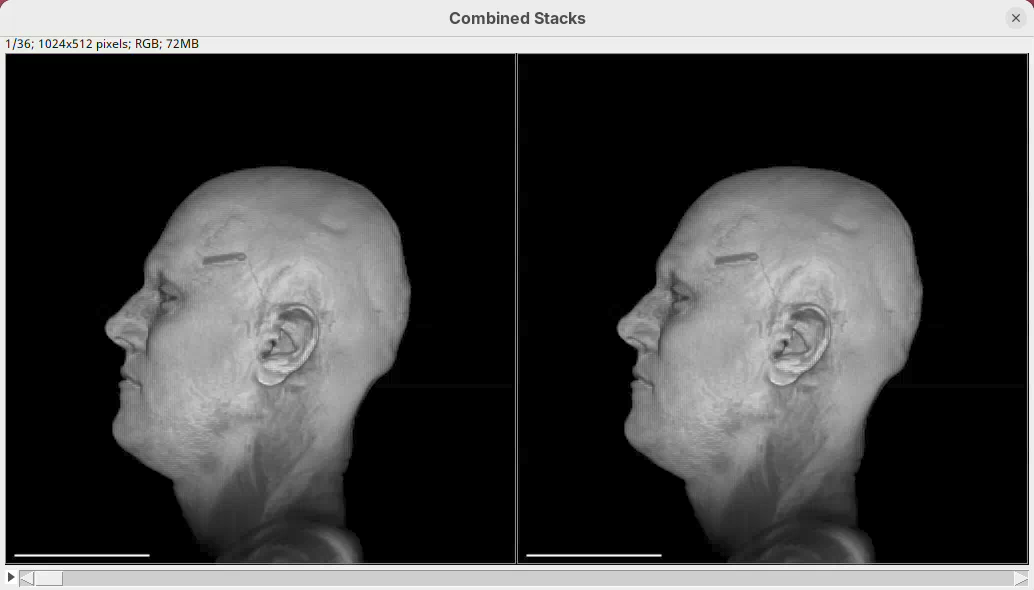

Add easing

The standard animation creates a linear rotation; every frame turns a fixed number of degrees. 3Dscript can add easing to create non-linear transitions by accelerating or decelerating the rotation.

- Type

easeat the end of the script sentence:

From frame 0 to frame 35 rotate by 360 degrees horizontally ease- Then, press

Run.

The left head is the one without easing (linear transition) and the right head is the animation with easing. Note how the right head accelerates the rotation at the beginning, turning much faster, and then decelerates towards the end of the rotation. Both end the rotation at the same time. Play both animations side-by-side to see the difference (it’s very clear, once you see it).